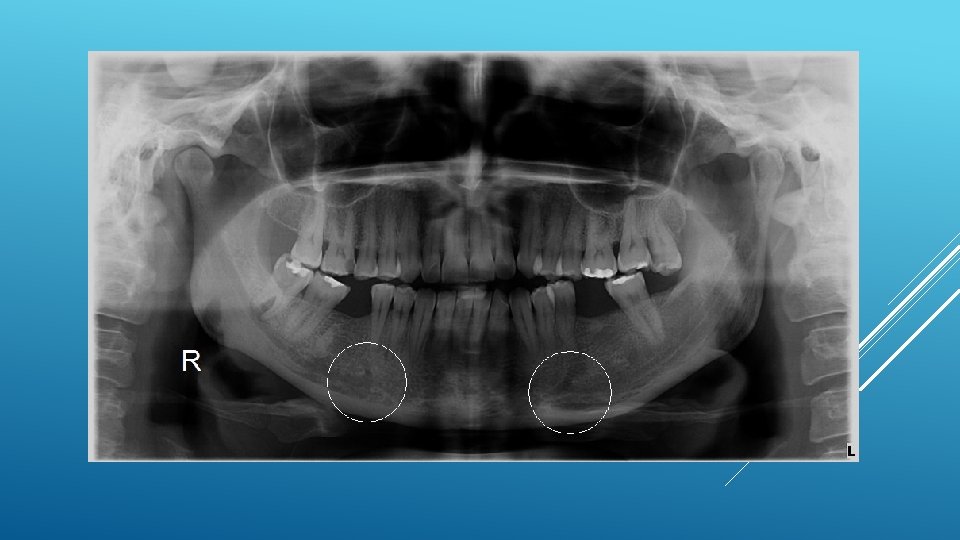

LOCATION AND DIMENSIONS OF THE MENTAL FORAMEN: A RADIOGRAPHIC ANALYSIS BY USING CONE-BEAM COMPUTED TOMOGRAPHY The majority of MF (56%) were located apically between the 2 premolars, and another 35. 7% of MF were positioned below the second premolar. On average, the MF was localized 5. 0 mm from the closest root of the adjacent tooth (range, 0. 3 -9. 8 mm). The mean size of the MF showed a height of 3. 0 mm and a length of 3. 2 mm; however, individual cases showed large differences in height (1. 8 -5. 1 mm) and in length (1. 8 -5. 5 mm). All mental canals exiting the MF demonstrated an upward course in the coronal plane, with 70. 1% of the mental canal presenting an anterior loop (AL) in the axial view. The mean extension of AL in cases with an AL was 2. 3 mm.

RELATIONSHIP BETWEEN THE POSITION OF THE MENTAL FORAMEN AND THE ANTERIOR LOOP OF THE INFERIOR ALVEOLAR NERVE AS DETERMINED BY CONE BEAM COMPUTED TOMOGRAPHY COMBINED WITH MIMICS The parameters were measured, and their values include mean (SD) anterior loop length, 1. 16 (1. 78) mm; anterior loop angle, 19. 13 (26. 89) degrees; inferior alveolar canal diameter, 3. 01 (0. 67) mm; height of the inferior alveolar canal, 10. 32 (1. 56) mm; 2 -dimensional mental foramen diameter, 2. 97 (0. 61) mm; 3 D mental foramen diameter, 2. 95 (0. 59) mm; 2 -dimensional vertical height of the mental foramen, 14. 67 (1. 67) mm; and 3 D vertical height of the mental foramen, 14. 61 (1. 69) mm. The mental foramen was located apically between the first and second premolars in 51. 67% and below the second premolar in 40. 83% of the cases.

THE MENTAL FORAMEN OR "THE CROSSROADS OF THE MANDIBLE. " AN ANATOMIC AND CLINICAL OBSERVATION] [ARTICLE IN FRENCH, GERMAN] THOMAS VON ARX 1 This paper presents a clinical and anatomical review of the mental foramen (MF) based on recent publications (since 1990). Usually, the MF is located below the 2 nd premolar or between the two premolars, but it may also be positioned below the 1 st premolar or below the mesial root of the 1 st molar. At the level of the MF, lingual canals may join the mandibular canal (hence the term "crossroads"). Accessory MF are frequently described in the literature with large ethnic variations in incidence. The emergence pattern of the mental canal usually has an upward and posterior direction. The presence and extent of an "anterior loop" of the mental canal may be overestimated with panoramic radiography. Limited cone-beam computed tomography currently appears to be the most precise radiographic technique for assessment of the "anterior loop". The mental nerve exiting the MF usually has three to four branches for innervation of the soft tissues of the chin, lower lip, facial gingiva and mucosa in the anterior mandible. The clinician is advised to observe a safety distance when performing incisions and osteotomies in the vicinity of the MF.

ANATOMICAL RELATIONSHIP BETWEEN MENTAL FORAMEN, MANDIBULAR TEETH AND RISK OF NERVE INJURY WITH ENDODONTIC TREATMENT he root apex of the mandibular second premolar (70 %), followed by the first premolar (18 %) and then the first molar (12 %), was the closest to the MF. Ninetysix percent of root apices evaluated were >3 mm from the MF. An AL was present in 88 % of the cases. Conclusions: With regards to endodontic treatment, the risk of nerve injury in the vicinity of the MF would appear to be low. However, the high incidence of the AL highlights the need for clinicians to be aware and careful of this important anatomical feature.

ASSESSMENT OF MORPHOLOGICAL AND ANATOMICAL CHARACTERISTICS OF MENTAL FORAMEN USING CONE BEAM COMPUTED TOMOGRAPHY All mental foramina were visualized. Regarding location, 49. 2% of the MFs were located between first and second premolars, 7. 7 distal and 39. 7% coincident to the apex of the mandibular second premolar. The mean MF opening angle was 45. 4° on the right side, and 45. 9° on the left. There were no statistically differences between gender groups with regard to the opening angle degree